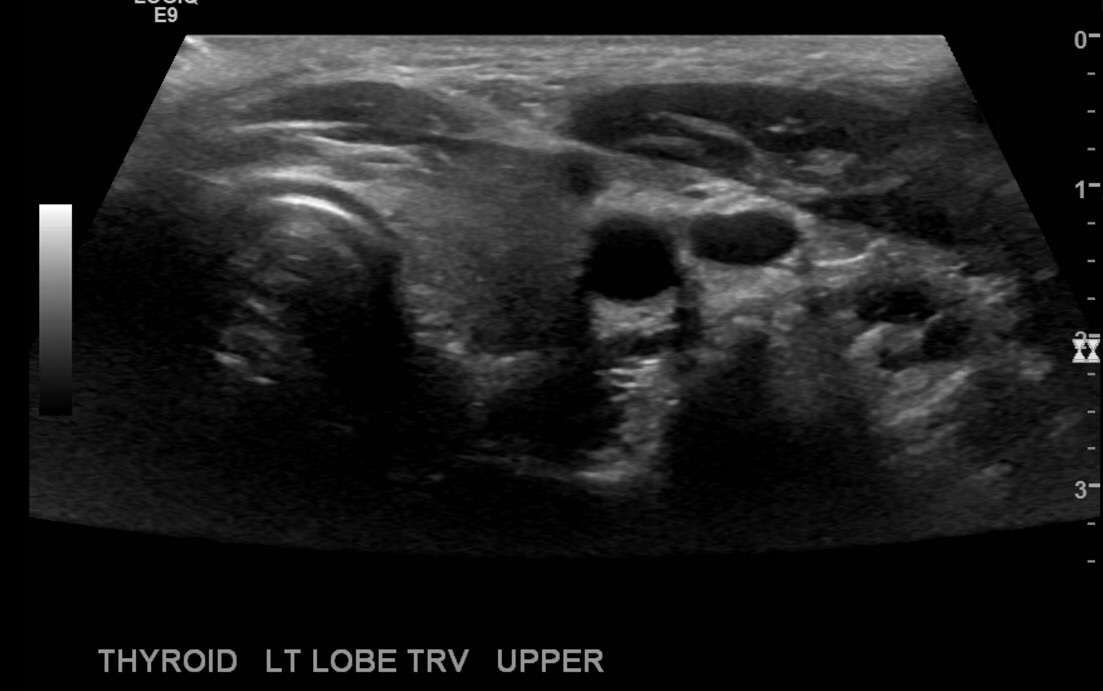

Turn the transducer counterclockwise and take transverse images at the middle of the rt lobe, superior and inferior.